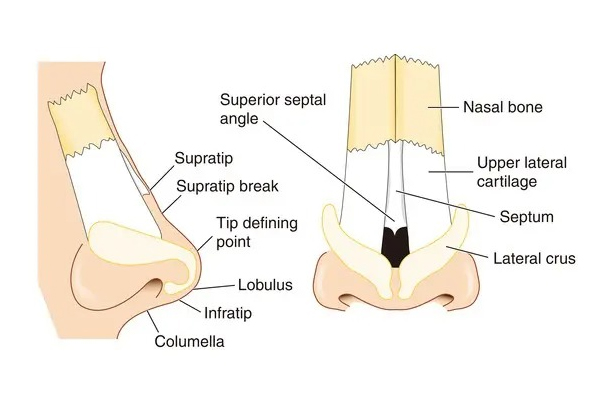

What Does Rhinoplasty Do?

Corrects Cosmetic Issues:

- Bulbous Tip: Reshapes a large, round, or poorly defined nasal tip.

- Upturned Nose: Adjusts an overly upturned nose or visible nostrils.

- Hooked Nose: Straightens a downward-curving nose.

- Droopy Nose: Lifts the nasal tip to eliminate a droopy look.

- Wide or Small Nostrils: Adjusts nostril size for better proportion.

- Nasal Bridge Irregularities: Smooths dips, bumps, or irregularities.

Corrects Structural and Functional Issues:

- Deviated Septum: Improves breathing by correcting a deviated septum.

- Facial Balance: Adjusts nose size to enhance facial symmetry.

- Blocked Nasal Passages: Opens obstructed nasal passages for easier breathing.

- Physical Examination – The surgeon assesses facial structure, nasal interior, and breathing function, especially for conditions like a deviated septum.